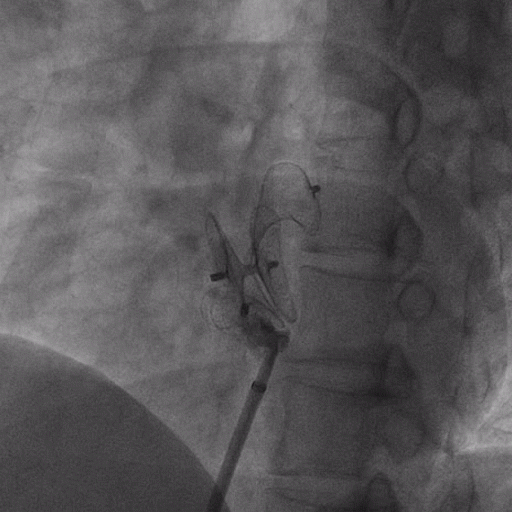

在獲得患者同意后,1月12日,尚福軍主任為患者進行了PFO封堵術(shù)。術(shù)中造影可見封堵器殘余漏,尚福軍主任用精湛的技藝,順利通過封堵器殘余漏裂縫,將右心導管從右房送入左房,且順利到達肺靜脈;遂行卵圓孔未閉封堵術(shù)后殘余漏再次封堵;且完美釋放PFO封堵器,可見兩封堵器呈“馬蹄蓮”狀,再次術(shù)中造影未見殘余漏。